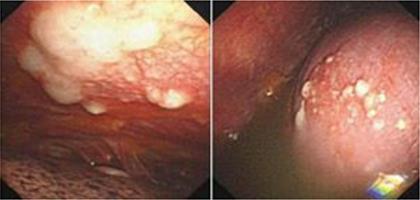

在肺癌进展的过程中,尤其是那些生长在肺部周边的病灶,癌细胞非常容易掉落至胸膜腔,并种植、生长在胸膜腔上,破坏血管、淋巴管,造成癌性胸腔积液。患者通常有咳嗽、咳痰、痰中带血等肺癌原发症状,血清肿瘤标志物水平可能会升高,胸部影像学检查可以发现病灶,甚至同时伴有肺癌远处转移相关症状。抽出胸水后,可以发现胸水常呈现血性,胸水中的肿瘤标志物亦升高,有时胸水中可查见癌细胞而获得确诊,必要时可行经皮胸膜活检检查来取得病理诊断,如仍诊断困难,可以借助内科胸腔镜检查术来明确诊断。

肺癌胸膜转移造成胸腔积液